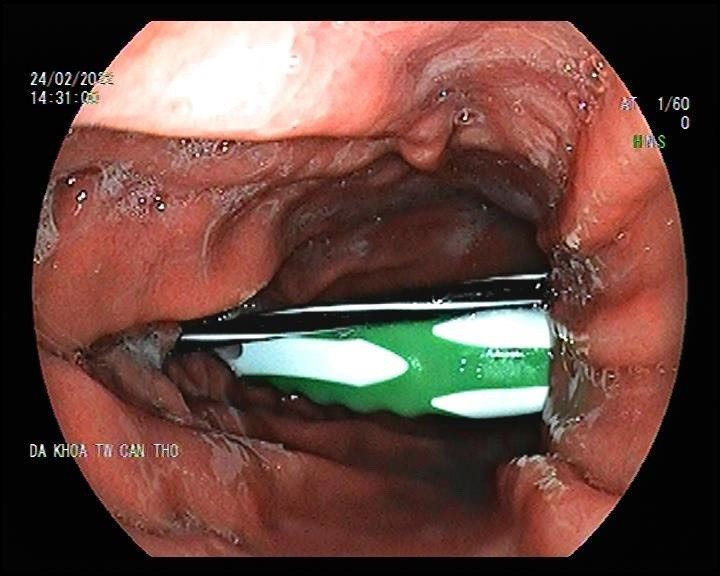

Thông tin từ Bệnh viện Đa khoa Trung ương Cần Thơ cho biết, các bác sĩ vừa nội soi can thiệp thành công dị vật là thân bàn chảy đánh răng và ruột bút bi trong dạ dày bệnh nhân nam 23 tuổi.

Kết quả nội soi cho thấy không chỉ có ruột bút bi dài khoảng 12cm mà còn có cả 1 thân bàn chải đánh răng dài khoảng 15cm, đường kính 1,5cm, đầu thân bàn chải cắm vào thành tá tràng.

Sau 15 phút nội soi, các bác sĩ đã can thiệp lấy dị vật thành công, đầu nhọn của dị vật gây ra vài ổ loét 10-15mm đáy giả mạc trắng, loét hành tá tràng. Bệnh nhân được chỉ định nhập viện theo dõi. Tuy nhiên, gia đình quyết định xin điều trị ngoại trú.